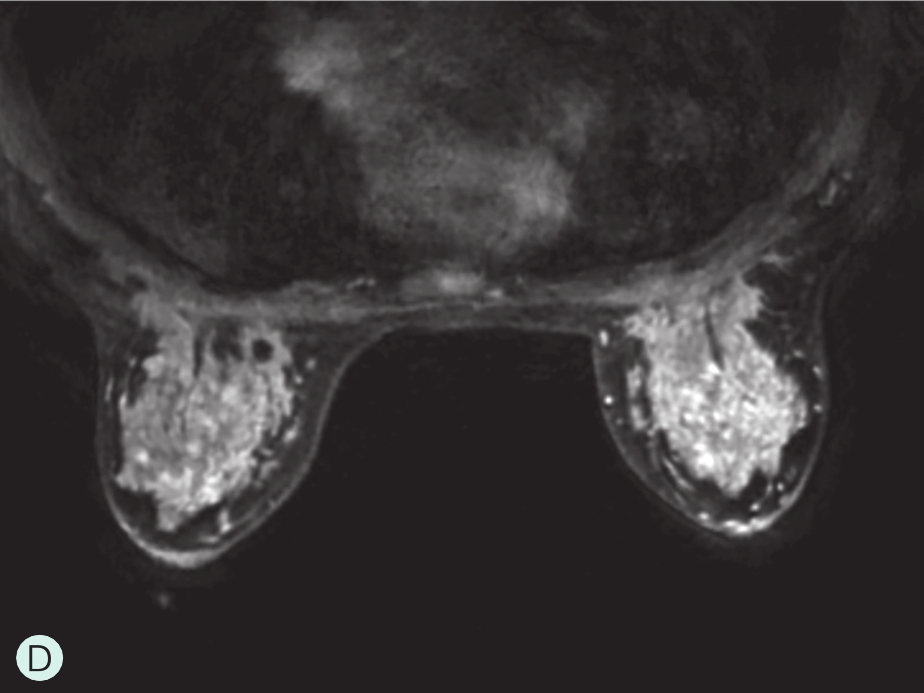

图1-4-4 增强MRI时不同乳腺腺体增强强度

A.MRI背景极少强化;B.MRI背景轻度强化;C.MRI背景中度强化;D.MRI背景重度强化